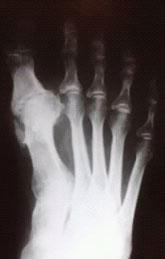

Для диагностики обязательно необходимо провести рентгенографию стопы. Этот метод позволяет выявить костные изменения, разрастания, пограничные дефекты суставных поверхностей, уменьшение суставных щелей, субхондральный склероз костной ткани и наличия кистовидных образований, что дает возможность провести дифференциальную диагностику.

На второй степени проявляется усиленный болевой синдром, которое ограничивает тыльное сгибание (разгибание) I пальца. Рентгенография выявляет субхондральный склероз, уплощение суставных поверхностей и сужение суставного пространства.

На третьей степени боли становятся постоянными и беспокоят даже в состоянии покоя. Тыльное сгибание пальца отсутствует, подошвенное ограничено. Возникает деформация сустава. На рентгенографических изображениях фиксируются костные наросты, выраженная деформация суставных поверхностей.